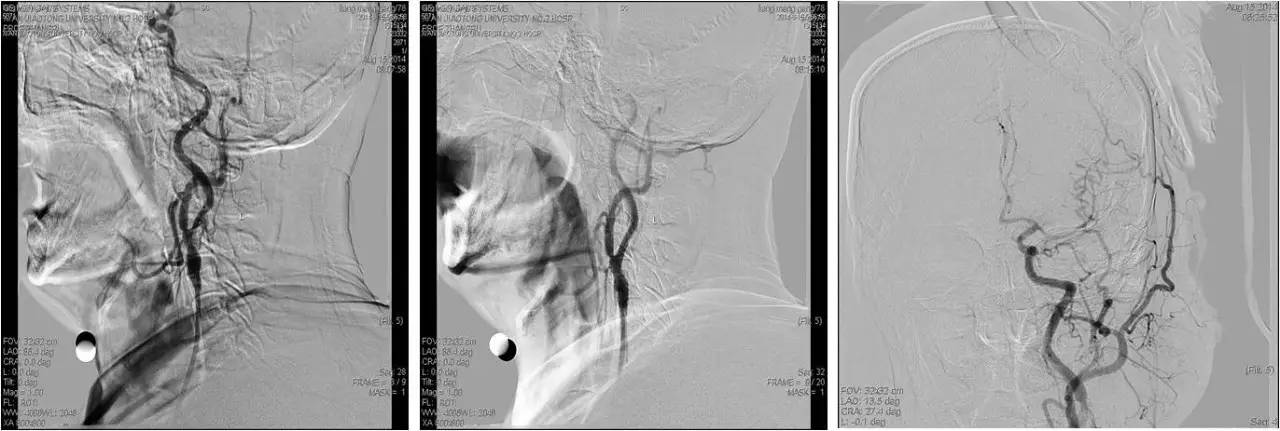

》急诊行DSA+动静脉联合溶栓+左侧颈内动脉狭窄球扩及支架成形术;

》乌拉地尔持续泵入,控制血压;

》rt-PA 5mg iv, 40mg ivd,维持1h;

》DSA:双侧颈内动脉起始部狭窄,狭窄率约80%,左侧大脑中前动脉显影差继而行超选择左侧颈内动脉动脉溶栓(rt-PA 5mg 推注),远端显影改善,行左侧颈内动脉狭窄球囊扩张及支架成形术。